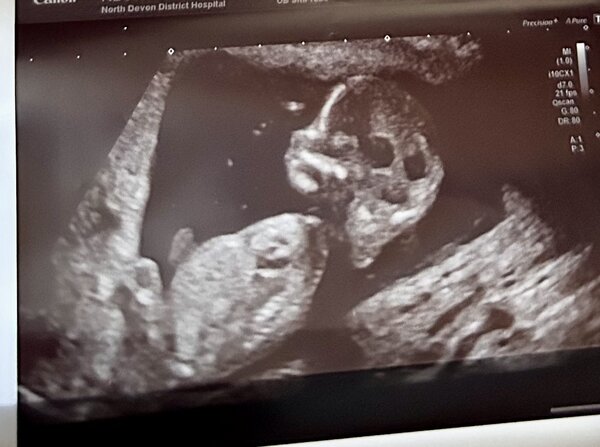

Bunu cektım şimdiden teşekkür ederim

Bitanem başka başka resimde atar mısın ama böyle olsun biraz daha yakın al tam göbeğin oralarını ki tam görelim.

Selamlar bitanem, hayır ortadan kaybolmadım da gülüm, bu resimden net bir şey diyemiyorum soldlaki yukarı doğru çıkıntı eğer resim hatası değil ise erkek gibi görüyorum. Başka resimler var ise ekleyin değerlendireyim. Yok diyorsanız bir dahaki doktor gidişinizde lütfen yakın bir resim isteyin. Nuba göre değerlendirecekler deyin. Sevgiler hayatım 🙂